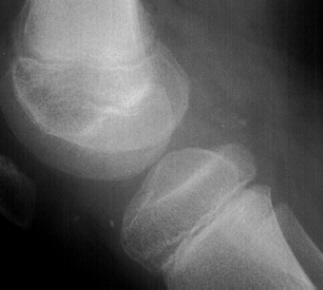

AP, lateral and obliques of the left knee showed an effusion with multiple radiodense bodies that were felt to be intraartictilar . No fractures or dislocations were evident. Comparison views of the right knee were unremarkable.

Evidence on imaging studies depends on the stage of disease. Until the loose bodies are ossified or calcified they may be radiographically invisible. This often leads to an unfortunate delay in treatment.